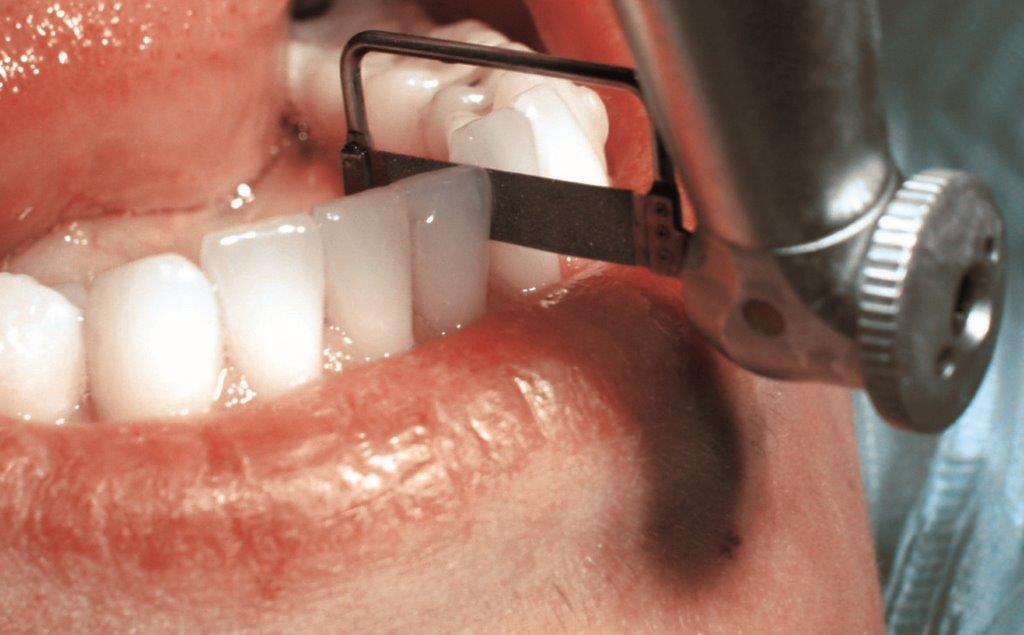

Source : Intensiv

D'autre part, nous avons les scies de stripping ou disques diamantés, un procédé mécanique optimal lorsqu'il faut gagner de l'espace. On utilise soit un contre-angle oscillant avec de petites scies, soit un contre-angle classique avec un disque diamanté. Lors de l'utilisation de ces instruments, qui sont plus puissants que le décapage manuel, il faut veiller à ne pas enlever trop d'émail dentaire.

Contre-angle orthodontique Swingle par Intensiv

Le Starter Kit contient un contre-angle orthodontique Swingle en deux versions différentes : avec ou sans lumière. Il dispose également d'une rotation libre et d'une position fixe pour ce type de traitement. Il est certain que cet instrument vous aidera à réduire avec précision les parties proximales de l'émail en vous offrant la plus grande sécurité. Les résultats attendus ? Une finition et un polissage parfaits.

Caractéristiques Contre-angle Swingle par Intensiv:

- Élimine la plaque sous-gingivale

- 12 positions différentes à 360°

- Petite taille et mouvement oscillant

- Finition des zones interdentaires et sous-gingivales

Voir le Contre-angle orthodontique Swingle